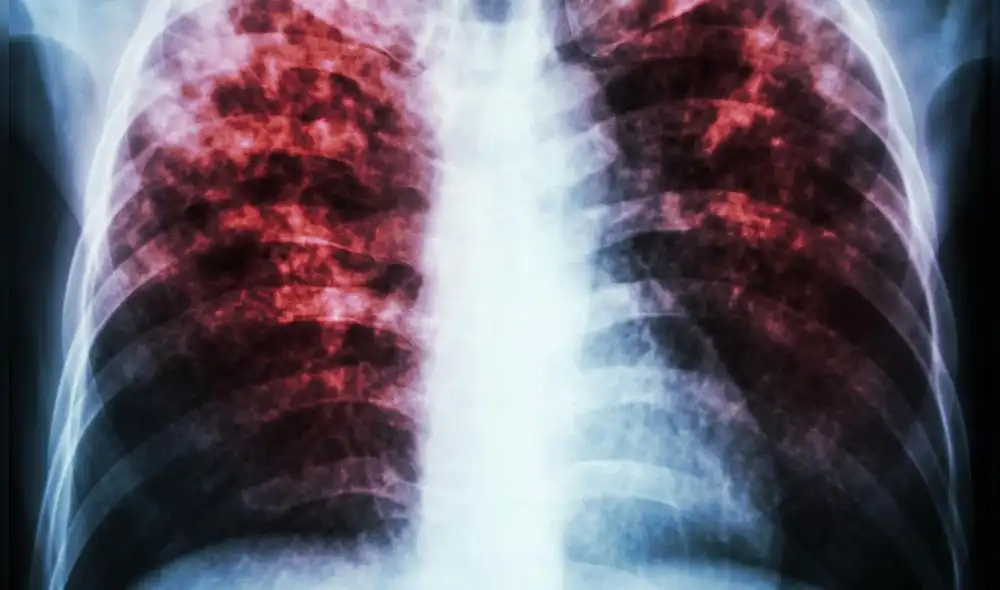

Tuberculosis: ¿Cómo prevenir esta enfermedad que se contagia en el Perú cada cuatro horas?